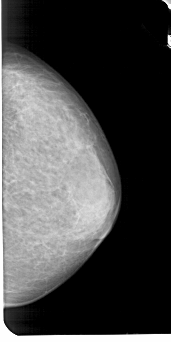

A_1947_1.RIGHT_MLO

RIGHT_MLO LINES 5491 PIXELS_PER_LINE 2761 BITS_PER_PIXEL 12 RESOLUTION 43.5 NON_OVERLAY